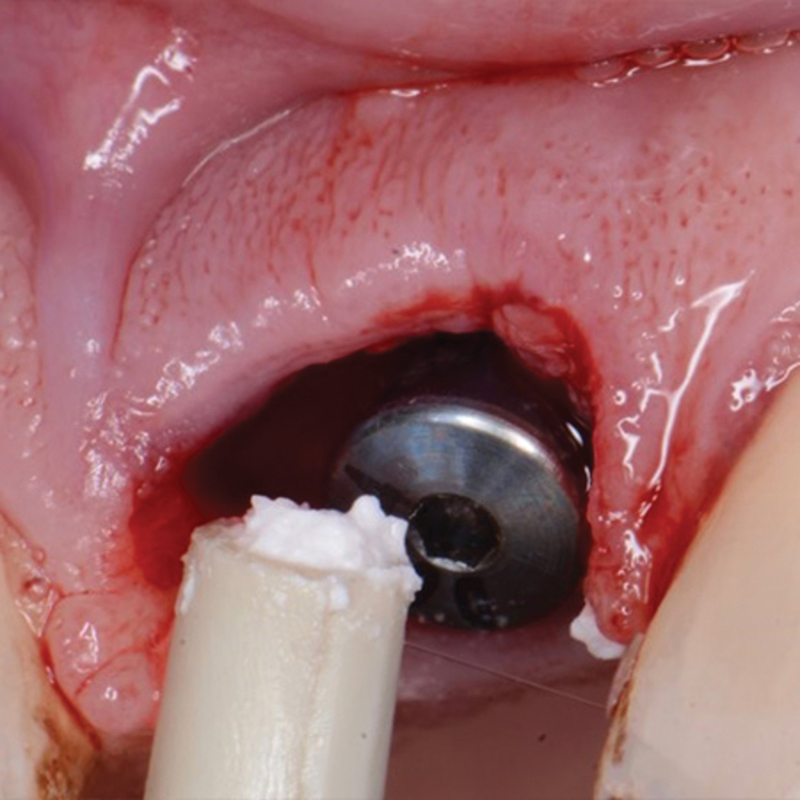

With resurgence in immediate tooth replacement therapy (ITRT) as a method of preserving both hard and soft tissues for improved aesthetic outcomes, this multicenter, prospective study looked at two novel products and their effect on those outcomes. Thirty-one maxillary single-tooth implants were included, of these 54.8% were central incisors, 25.8% lateral incisors, and 19.4% canines. Three complications were reported; one case nondraining fistula, one case a nonseated provisional restoration, and one case a fractured zirconia abutment. The definitive restorations were delivered between 4 hours and 18 months postimplant placement and all restorations were screw-retained. ITRT is frequently utilized when a tooth to be extracted will be replaced by an implant aiding in preservation of the hard and soft tissue that may be lost due to resorption during healing of the extraction socket. The narrower neck region of the Inverta implant results in thicker crestal bone around the implant, where loading under function occurs. Grafting that area around the implant at placement with EthOss results in more predictable bone stability in the long term.

随着即时牙齿替代疗法(ITRT)作为一种保存硬组织和软组织以改善美学结果的方法的复兴,本多中心前瞻性研究观察了两种新产品及其对这些结果的影响。上颌单牙种植体31颗,其中中切54.8%,侧切25.8%,犬齿19.4%。报告3例并发症;1例非引流瘘,1例非坐位临时修复,1例氧化锆基台骨折。最终修复体在种植体放置后4小时至18个月之间交付,所有修复体均采用螺钉保留。在拔牙槽愈合过程中,为了保护因吸收而丢失的硬组织和软组织,ITRT常用于用种植体代替待拔牙。Inverta种植体较窄的颈部区域导致种植体周围的嵴骨较厚,在那里发生功能负荷。使用EthOss在植入时将植入物周围的区域进行移植,可以获得更可预测的长期骨稳定性。